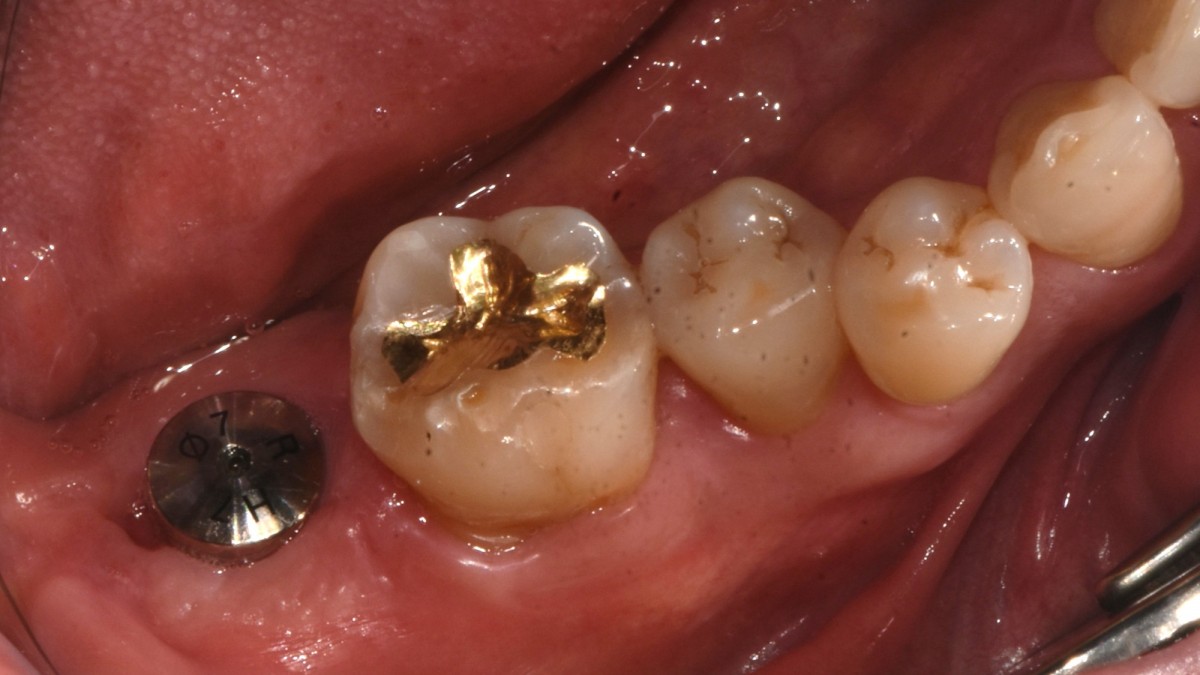

Single implant (staged) Arum NB1, f/u

A 47-year-old male patient had a crown with an ill-fitting margin and crack-tooth syndrome in the lower 2nd molar. No systemic issue.